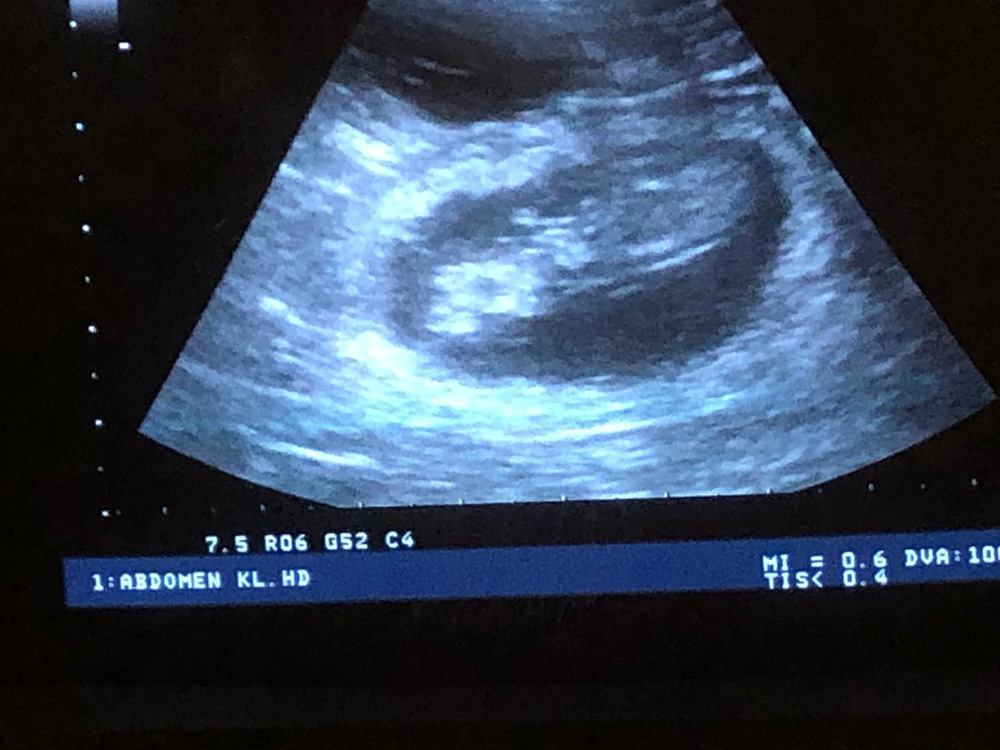

Drachtecho